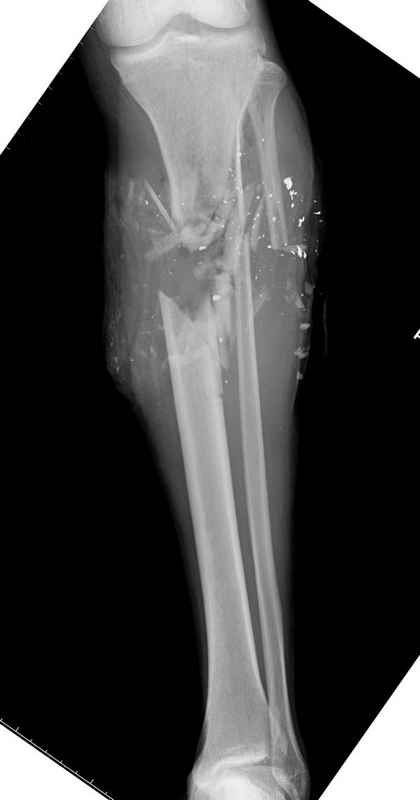

огнестрельный перелом голени |

Уважаемые коллеги, Современная тактика лечения огнестрельных переломов вызывает споры. Опыты многих стран доказывает, что открытые переломы можно успешно лечить с применением внутренних металлических конструкций, включая гвозди. В западных странах более 25 лет эту методику применяют для лечения огнестрельных переломов. После применения адекватных методов по предупреждению осложнений, например, после промывания ран, огнестрельные переломы можно стабилизировать без боязни инфицирования. Здесь представлен больной 27 лет с ранениями, включая огнестрельный перелом большеберцовой кости. Стандартный аьгоритм: 11.08.09 доставлен в операционную, Irrigation&Debridment c фиксацией Наружным Фиксатором и вакуумирование VAC; службой травмы пройзведена ангиография с негативным результатом. (снимки 1-10) 14.08.09 повторная Irrigation&Debridment (чувстительственность из раны негативная) со сменой фиксации на медуллярный гвоздь и вакуумирование VAC 18.08 и 21.08.09 Irrigation&Debridment с сменой е VAC, после высеялся MRSA in thio т.е. на специальных срезах небольшое количество (11-13) 25.08.09 повторная Irrigation&Debridment. Пластик хирург не стал рисковать с Soleus flap из-за отечности, и применен Gastric flap, кожная пластика на медиальную и латеральную рану; аллографт из костных стружек с BMP. Поверхность вакуумирована VAC системой на 4 дня (14-16) Финальные снимки сделаем на днях. Djoldas Kuldjanov, MDDepartment of Orthopedic SurgerySt. Louis University Medical Center